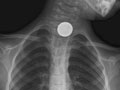

• Encontrar objetos extraños, como monedas u otros trozos pequeños de metal, en el conducto que va al estómago (esófago), las vías respiratorias o los pulmones. Es posible que en una radiografía de pecho no puedan observarse alimentos, nueces ni fibras de madera. Vea una radiografía de una moneda en el esófago.

Se observa un objeto extraño en el esófago, en las vías respiratorias o en los pulmones.